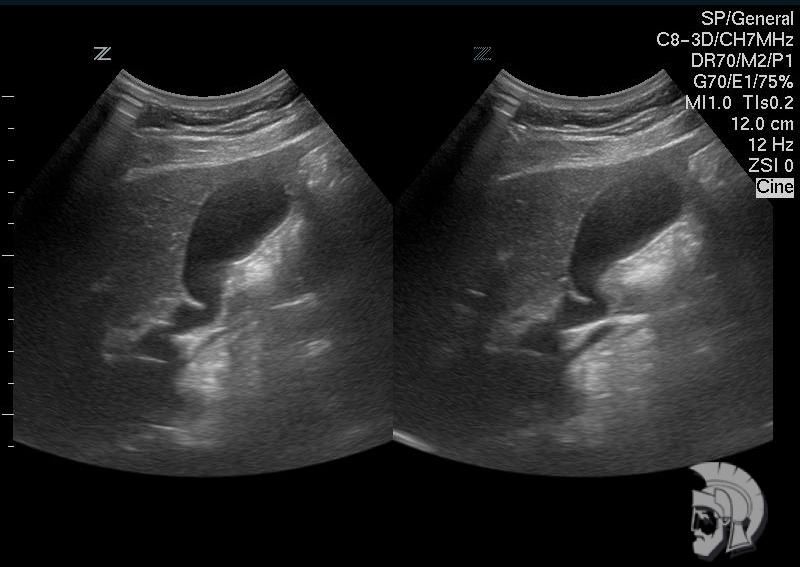

| Фото желчного пузыря. Желчный пузырь с перетяжкой у мужчины 28 лет. Желчный пузырь определяется в виде «тёмного» образования S - образной формы. Перетяжка определяется на границе средней и нижней третей желчного пузыря в виде выступающей «светлой» полоски |